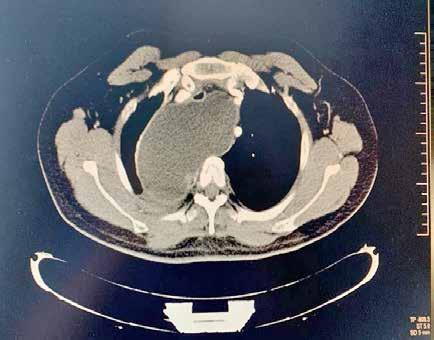

Figura 1. (Izq.) radiografía de tórax en proyección anteroposterior (AP) al ingreso en UCI-N para comprobación de sonda nasogástrica sin hallazgos significativos. (Der.) Radiografía de tórax AP a las 16 horas de vida donde se objetivan tenues focos de aumento de densidad de distribución difusa, alguno de ellos, como el localizado en campo superior izquierdo, con broncograma aéreo.

Figura 2. (Izq.) radiografía de tórax en proyección AP a las 36 horas de vida donde se objetiva neumotórax de nueva aparición (flechas azules) y una zona de hiperclaridad alrededor de la silueta cardíaca que sugiere importante neumomediastino (estrellas amarillas). (Der.) TC de tórax sin contraste intravenoso en ventana de pulmón que confirma la presencia de neumomediastino (estrella amarilla). Se objetivan focos de consolidación periféricos y bandas lineales de densidad aire paralelas y adyacentes a las vainas broncovasculares (flechas amarillas).